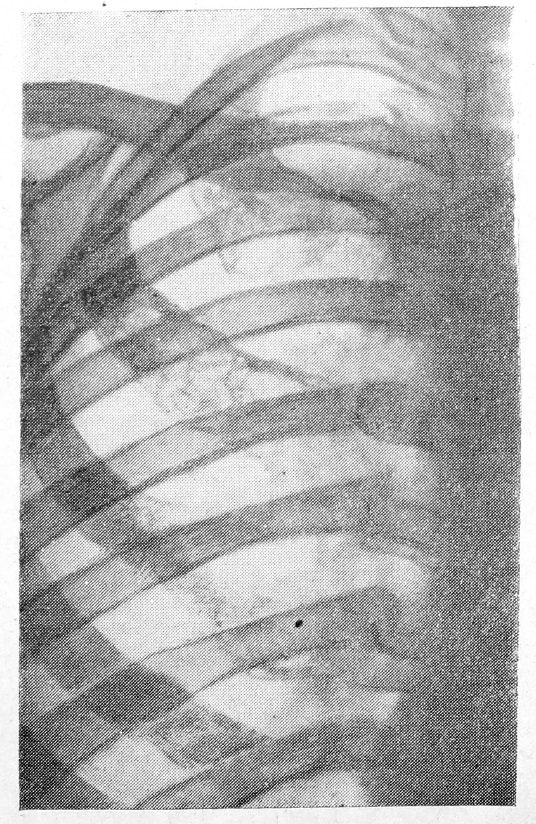

Рис- 1. до лечения

На контрольных рентгенограммах вскоре после лучевой терапии, несмотря на удовлетворительный клинический результат, перемен в большинстве случаев не отмечалось. При рентгенологическом контроле через 5—6 месяцев, чаще через 8 месяцев, наблюдалось отложение солей кальция — развитие реактивного »остеосклероза в месте поражения (рис. 1, 2). По нашим данным, наиболее отчетливое склерозирование пораженной кости происходило после облучения плоских костей (ребра, грудины, лопатки).